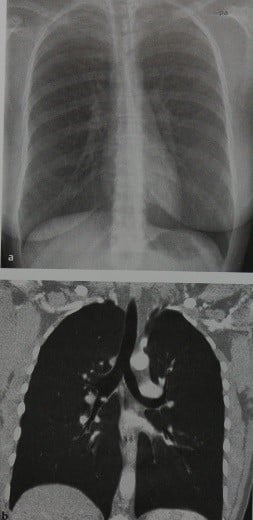

Фотографии заболеваний бронхолегочной системы